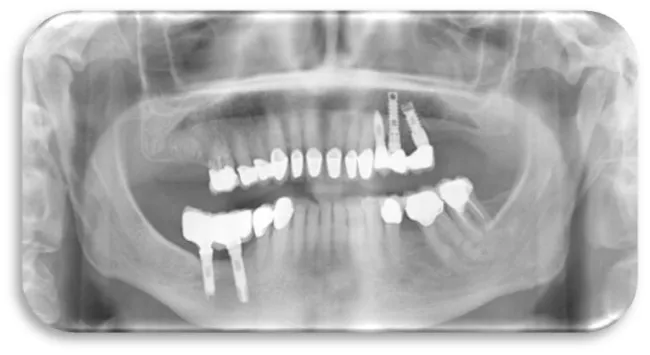

The fourth clinical case was a 51 year old male patient. He is an active cigarette smoker and has a cardiovascular disease. A dental implant is placed in the upper right quadrant, the exact position is 14. The role of dental implant is to compensate the upper first right premolar. After 12 months from the dental implant placement, a control panoramic image was made in order to see the condition of the dental implant. In the orthopantomographic image below (Figure 26), the extensive bone resorption was noted in both jaws, which is particularly expressed in the maxilla.

The fifth clinical case is female patient at the age of 48, without any systemic disease but an active cigarette smoker. Four dental implants were placed, three of which ware in the maxilla, and one in mandible. In the upper right quadrant, two dental implants were placed and they compensate the lost first molar. Two crowns with premolar size were placed on two dental implants, in order to avoid excessive overload due to the masticatory pressure that mostly affects that area.

In the upper left quadrant on posterior region, one more titanium dental implant was placed, which compensates the lost first molar. In the lower left quadrant on the posterior region, another dental implant was placed instеad of the lower first natural molar. After 9 months a control panoramic X-ray was made in order to follow the condition of the bone tissue in the both jaws. From the figure 27 it’s evident that bone resorption is more expressed in maxilla than in mandible. The larger bone defect was noted in the upper posterior right quadrant, where two dental implants are placed next to each other.

The sixth clinical case was a 29 year old female patient with excellent health condition. Three dental implants were placed in the lower right quadrant. Dental implants compensate previously lost first and second permanent molars. On the panoramic image below (Figure 28), could can be seen that bone resorption was more pronounced in the mandible, especially in the lower right posterior quadrant, than in the maxilla. The panoramic record was done after 11 months of dental implants placement (Figure 28).